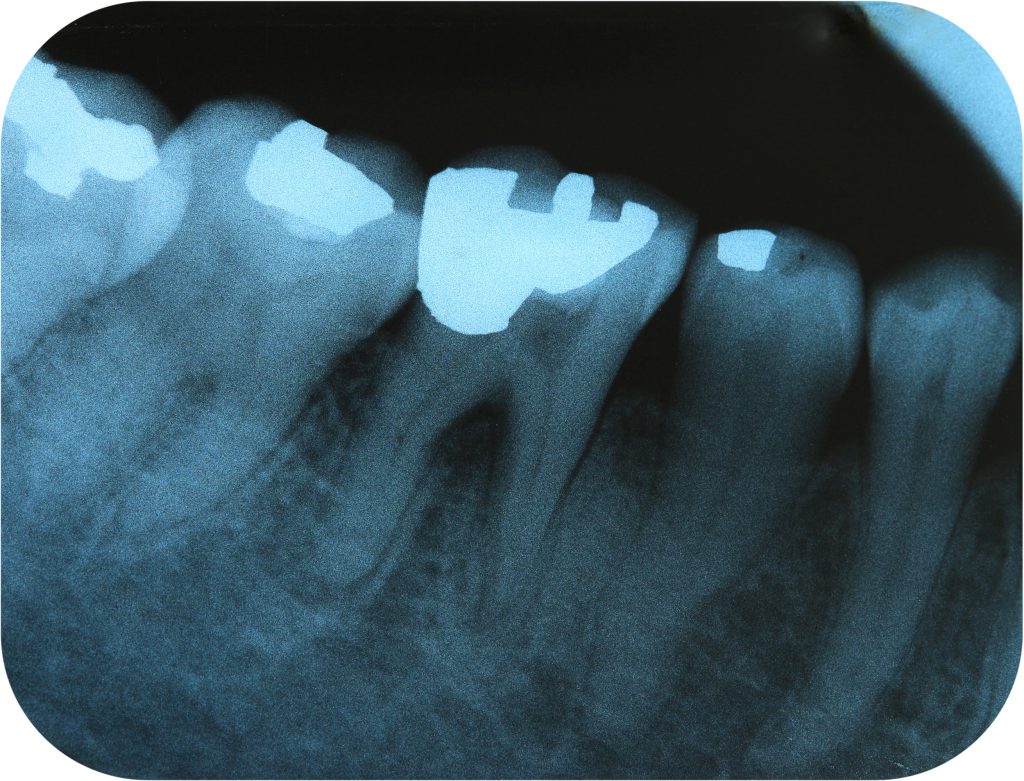

Röntgenbild von menschlichen Backenzähnen mit Füllungen, zeigt Zahnstruktur und zahnärztliche Eingriffe.Amalgam ist ein Ober­be­griff für Legie­rungen mit Queck­silber, welches in der Rein­form ein hoch­gif­tiges Schwer­me­tall ist. Wenn durch Karies ein Loch im Zahn entsteht, kann Queck­silber mit Silber, Zinn und Kupfer vermischt und als Füllungs­ma­te­rial einge­setzt werden. Schon seit 1820 verwenden Zahn­ärzte Amalgam stan­dard­mäßig in Europa.